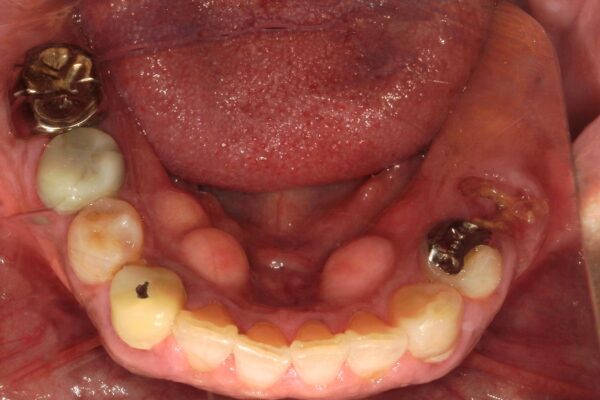

Before

| 通院目的 | 歯がなくなって食べ物が噛めなくなった。 かたい物が噛みづらく、前歯で噛んでいるのでインプラントにしてしっかり噛みたい。 |

| 処置内容 | 左下第二小臼歯が骨縁下う蝕で保存不可となり、元々欠損状態の第一大臼歯と共に抜歯即時インプラント埋入手術を行い、3ヶ月半後に、型取りを行い最終的な補綴物を製作・装着しました。 |